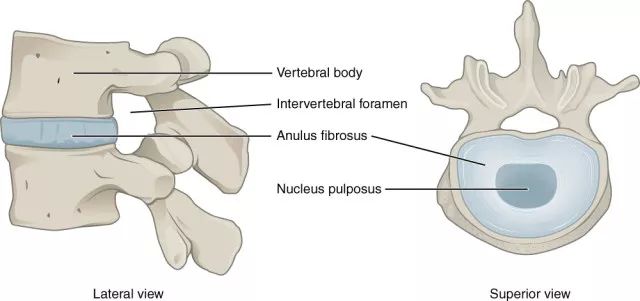

椎间盘是连接相邻两个椎体的纤维软骨盘,由两部分组成,周围部为纤维环(Anulus fibrosis)是由数十层环状及放射状的胶原纤维及弹性纤维交织而成按同心圆排列的致密组织,富于坚韧性,将各椎体紧密牢固的连接成一体,保护髓核并限制髓核向周围突出。

图 1 正常椎间盘示意图,椎间盘由周围的纤维环和中心的髓核组成